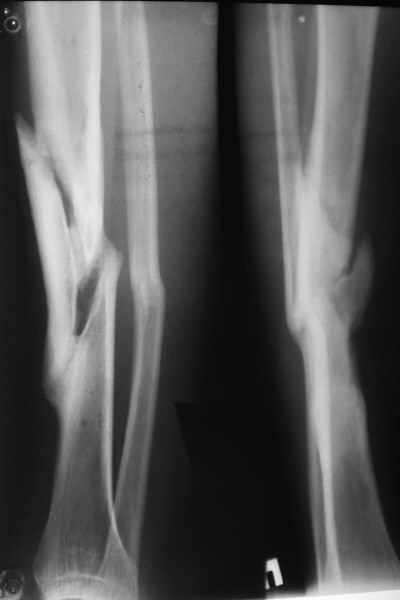

Уважаемые коллеги! На консультации больной предъявляет жалобы на хромоту (укорочение - 2см), боль в месте перелома при нагрузке (спортсмен).

Семь месяцев назад получил закрытый перелом, лечился консервативно в одной из больниц города. Как-бы кто лечил? Сам склоняюсь к LCP с костной пластикой.

При невозможности или чрезмерной травматичности одномоментного восстановления длины можно пойти двухэтапно (аппарат, потом гвоздь). Похожий пример см. тут. Прошло уже года полтора после остеосинтеза. Может, коллега Зырянов покажет годичный результат, если есть?

Александр Николаевич, к сожалению больной не является на контрольные осмотры. Я последний раз видел больного, когда прошло 7 месяцев после операции БОС. У него все хорошо. Каких либо жалоб и ограничений в нагрузке нет. Высылаю снимки до операции и последние снимки.